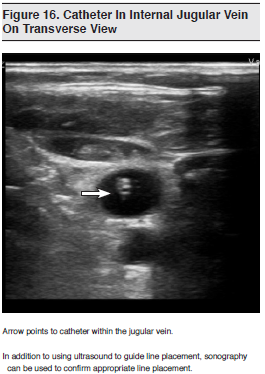

Central venous catheterization is a procedure that is often required for critically ill ED patients. Although this is generally a safe procedure, the complication rate has been reported to vary from 3% to as high as 20% in some studies.119-121 Complications range from minimal to life-threatening and include arterial cannulation, pneumothorax, cardiac tamponade, air embolus, hematoma formation, and injury to adjacent neurovascular structures. The goal of real-time ultrasound is to enable the operator to visualize the target vessel and surrounding structures before and during needle insertion. (See Figure 16.) While the traditional landmark technique is successful in many cases, factors such as patient body habitus, prior cannulation, the presence of scar tissue or thrombus, and variant anatomy can all make the landmark approach to vascular access more difficult.

The potential limitations of ultrasound are outweighed, however, by the evidence supporting its routine use for central line placement. The role of real-time ultrasonographic guidance has become so well-established in the medical literature that it is now recommended by multiple societies, including the Agency for Healthcare Research and Quality,131 the American College of Emergency Physicians,1 the American College of Chest Physicians,132 and the British National Institute for Clinical Excellence.133 Given this overwhelming support and the potential for error reduction as compared with traditional landmark techniques for line placement, ultrasound guidance for central venous catheterization should be used whenever possible and is considered by many to be the standard of care.